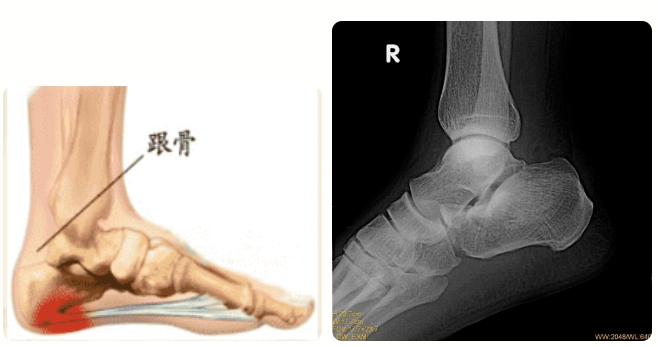

跟骨骨折后该怎么护理呢?好色tv 手足外科教你几个小妙招